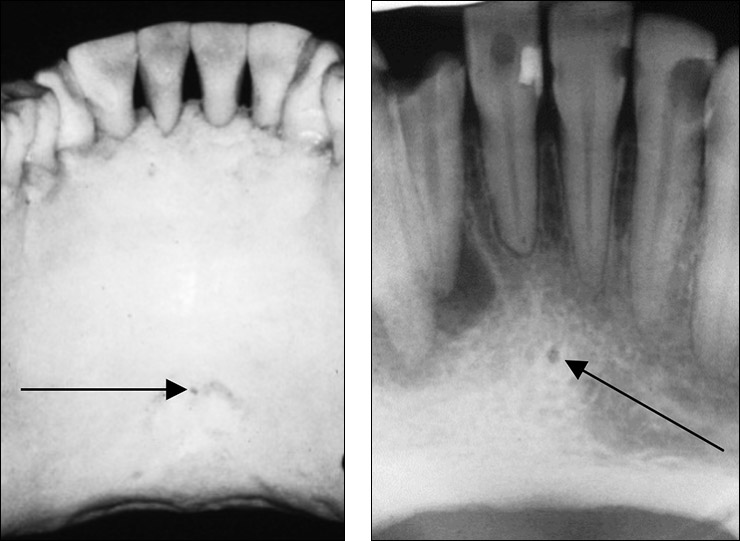

Incisive foramen / nasopalatine foramen

Appears between the roots of the central incisor & looks like a round oval less than 1 cm in diameter

Seen on maxillary central incisor PA’s